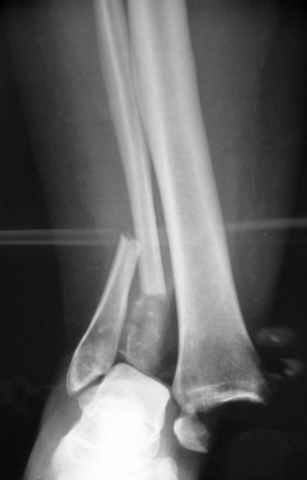

Dear all,40 y.o. man had sustained this terrible fracture falling from a motorbike.

Closed fracture.

This is really Pilon Fx (C3.3; the high energy and the extent of distal tibia comminution are defining it).